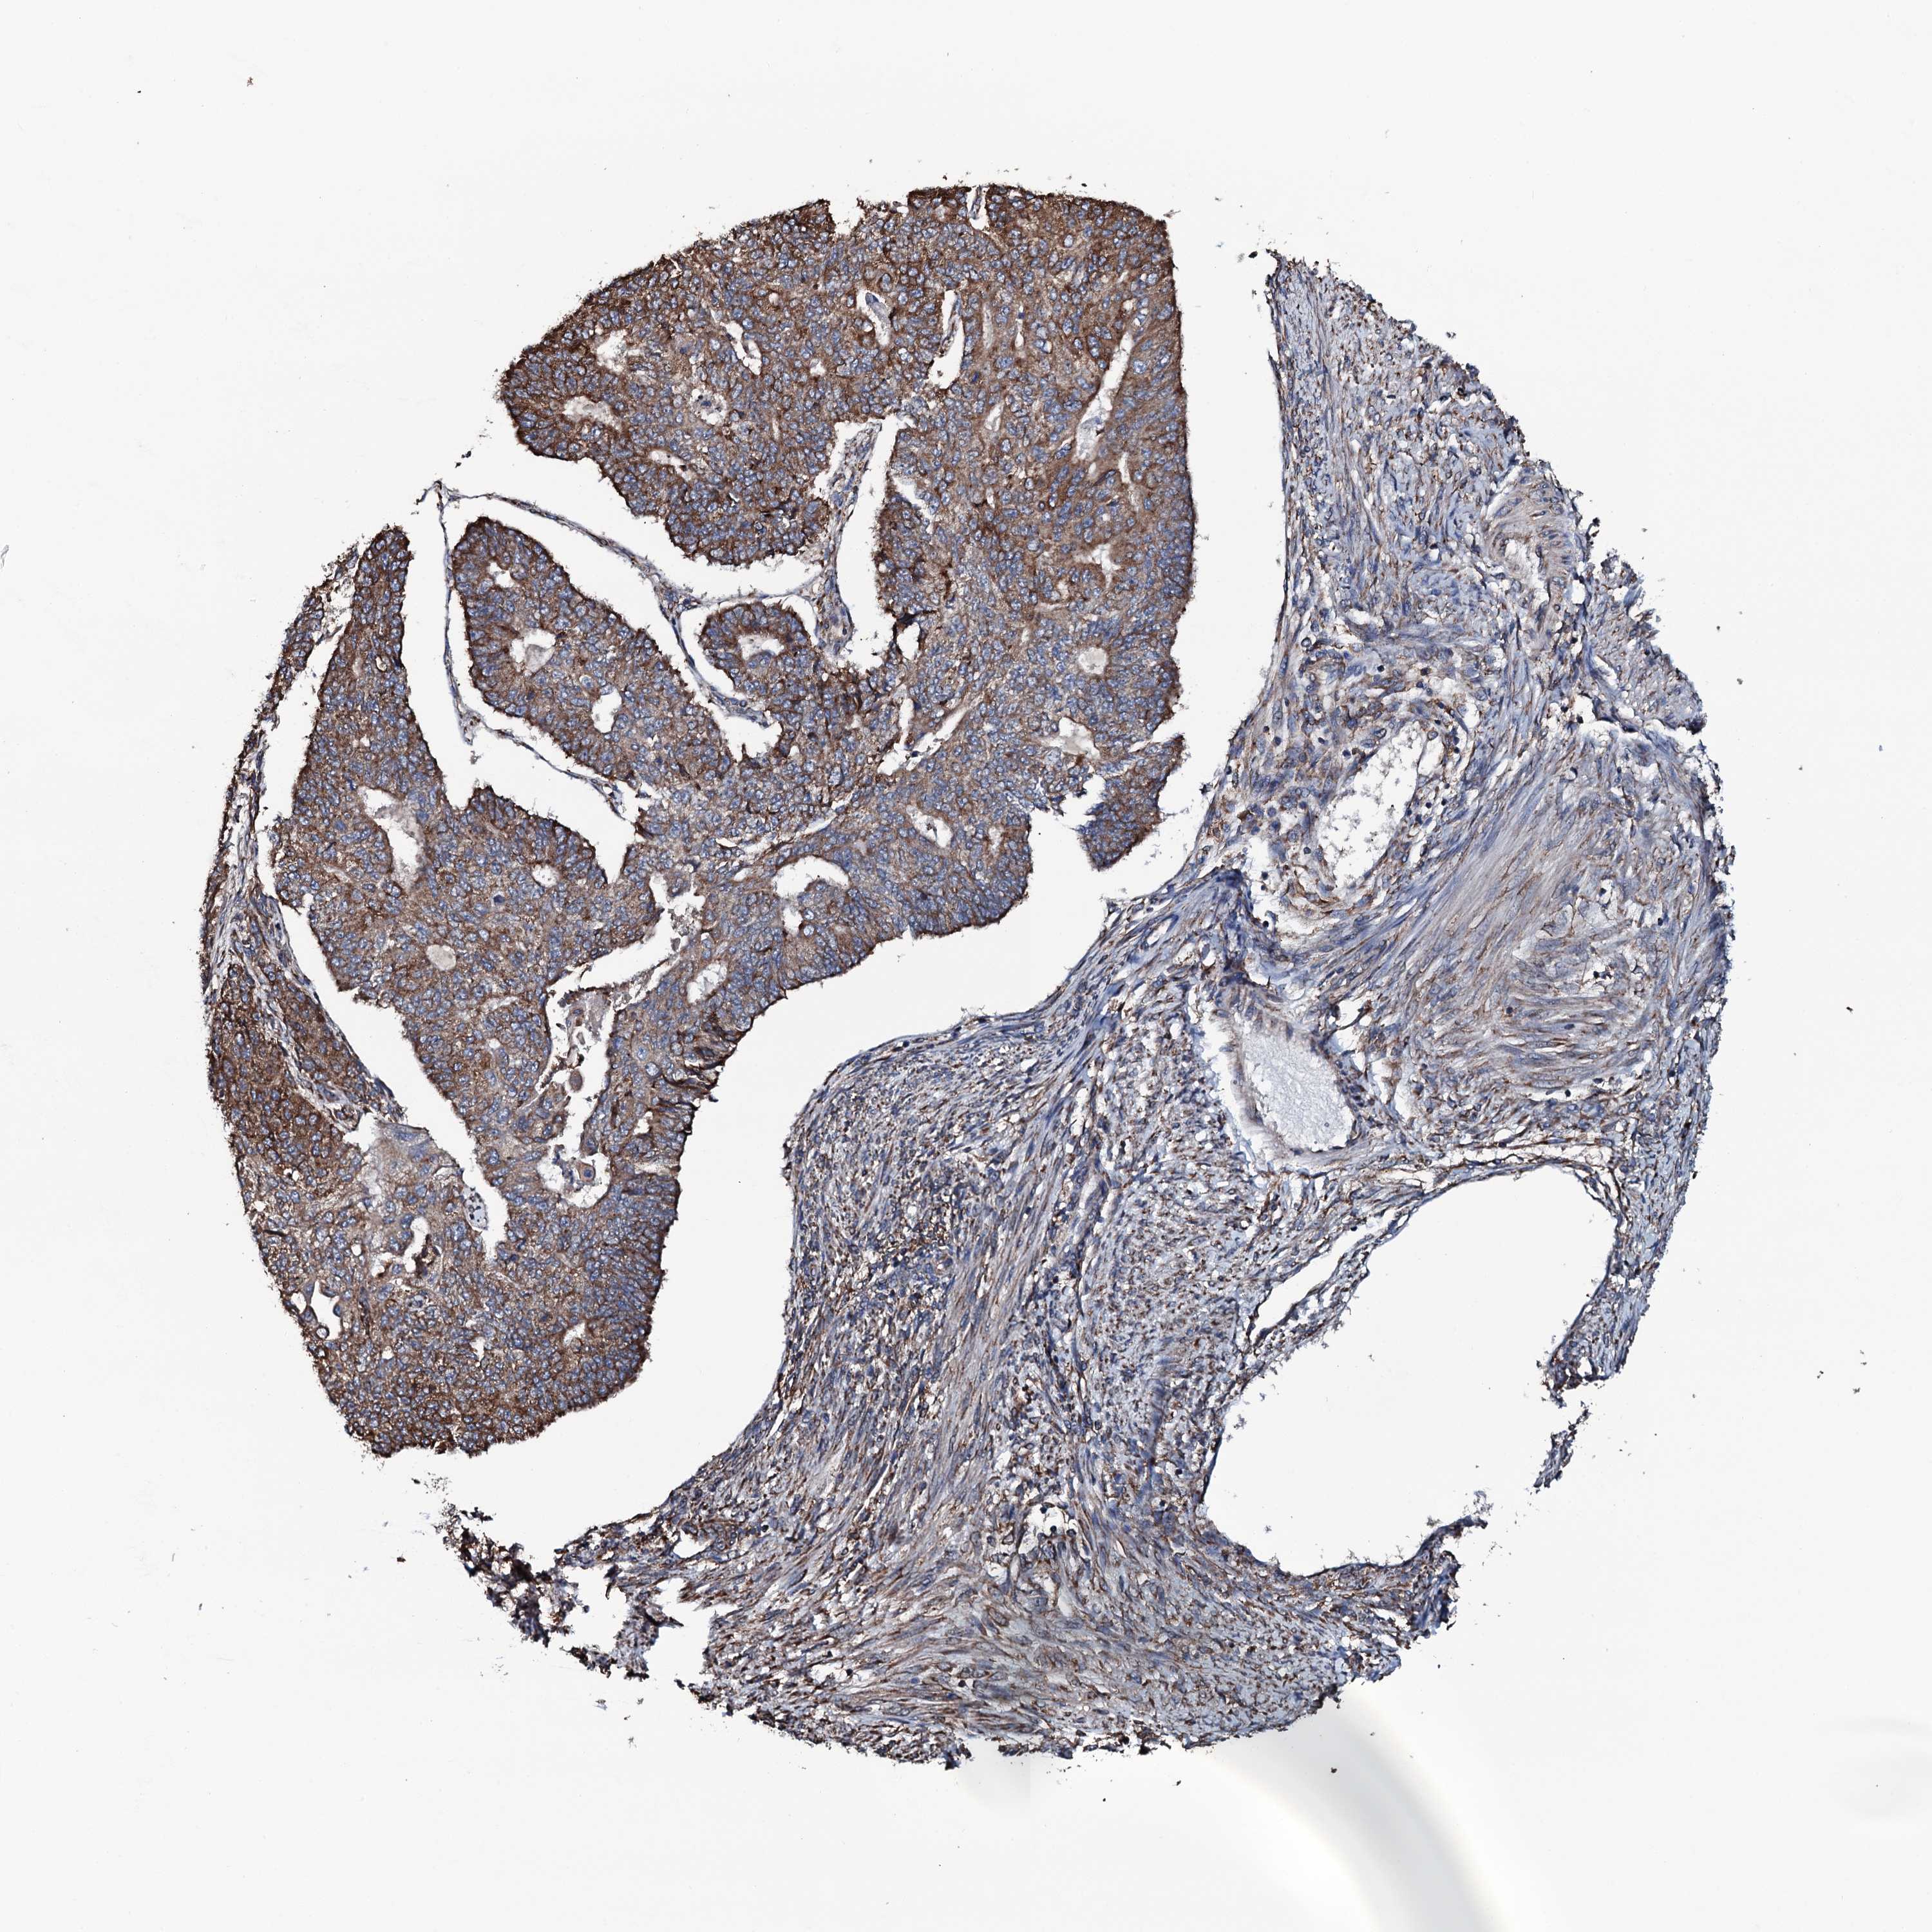

ENDOMETRIAL CANCER - Protein expressioni

A mouse-over function shows sample information and annotation data. Click on an image to view it in a full screen mode. Samples can be filtered based on level of antibody staining by selecting one or several of the following categories: high, medium, low and not detected. The assay and annotation is described here.

Note that samples used for immunohistochemistry by the Human Protein Atlas do not correspond to samples in the TCGA dataset.

Antibody stainingi

Antibody staining in the annotated cell types in the current human tissue is reported as not detected, low, medium, or high, based on conventional immunohistochemistry profiling in selected tissues. This score is based on the combination of the staining intensity and fraction of stained cells.

Each image is clickable and will lead to virtual microscopy that enables deeper exploration of all samples and also displays staining intensity scores, fraction scores and subcellular localization as well as patient and tissue information for each sample.

Antibody HPA040727

Staining

High

Medium

Low

Not detected

Intensity

Strong

Moderate

Weak

Negative

Quantity

>75%

75%-25%

<25%

None

Location

Nuclear

Cytoplasmic/membranous

Cytoplasmic/membranous,nuclear

Adenocarcinoma, NOS